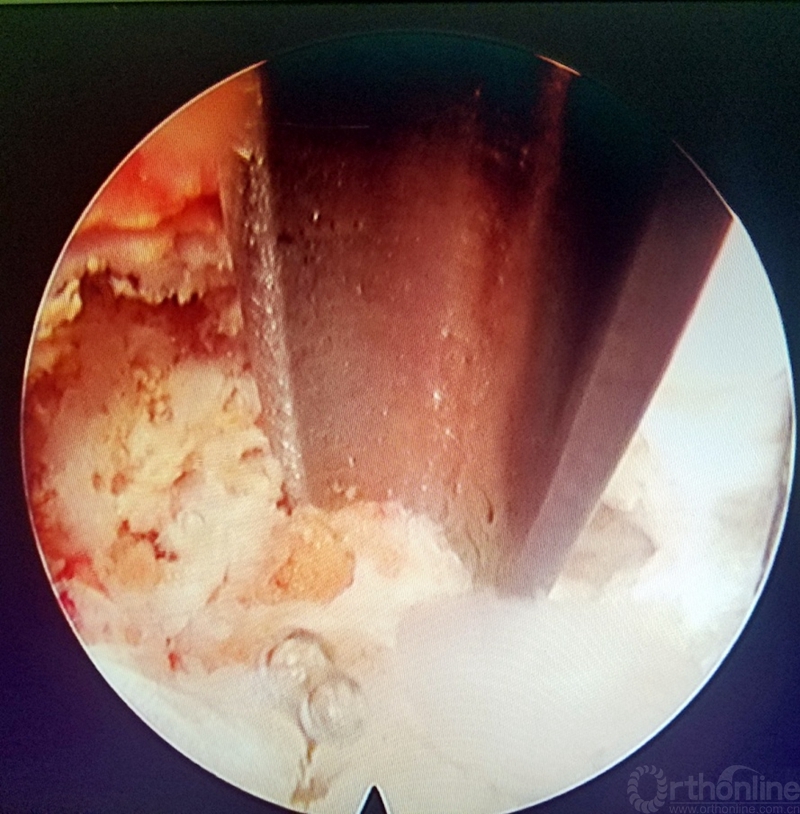

第三步:置入内镜系统,逐步旋转通道,找到上关节突和上下椎体后缘,判断好解剖位置及椎间隙位置,镜下用磨钻或骨刀直视下行椎间孔的成型,根据需要选择性去除部分关节突,达到工作通道逐步推进椎管,看见黄韧带和椎间盘即可(盘黄间隙)。如图3-7

图3 椎间孔成型前

图4 直视下行关节突去除

图5 直视下行关节突去除

图6 直视下椎间孔成型后

图7 逐步推进通道到达盘黄间隙